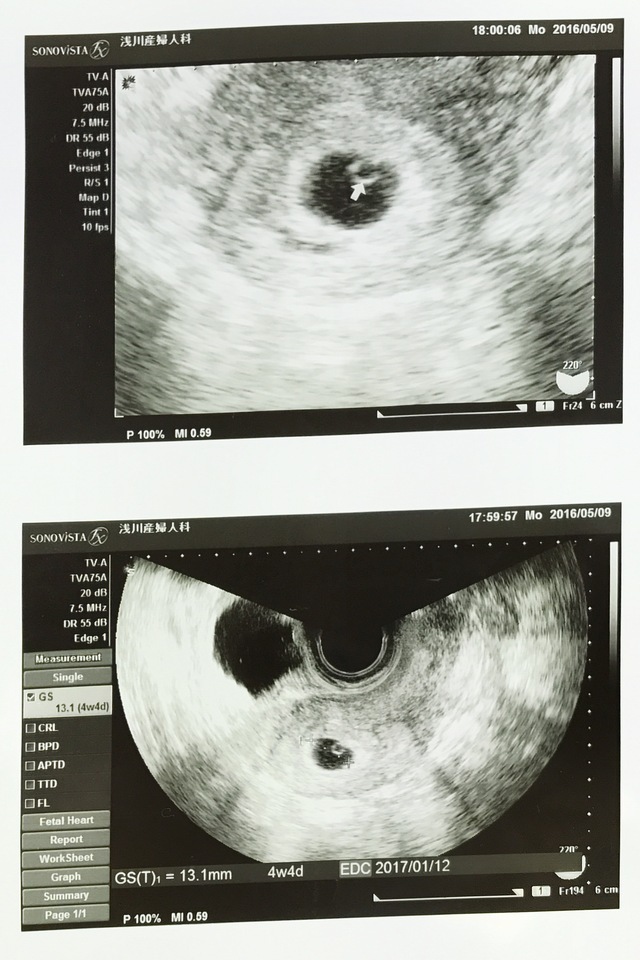

4週4日(4w4d・女の子)|あいまま さん(24歳)

エコー写真撮影時のエピソード:

1ヵ月生理が来なかったので、市販の検査薬で検査をしたところ+になり、すぐに産婦人科へ。

子どもはいつか欲しかったので、妊娠がわかって嬉しい気持ちがわきました。一方で、ちょうど仕事も脂が乗り始めて楽しくなってきた時期だったので、どうしようという気持ちが入り交じりながら診察を待っていたのを覚えています。

産むと決めてからは、ぎりぎりまで仕事しながらも楽しくマタニティーライフを送ることが出来ました。 楽しみと不安がありながら、出産を迎え、今ではわが子に対して「生まれてきてくれてありがとう」という感謝しかありません。